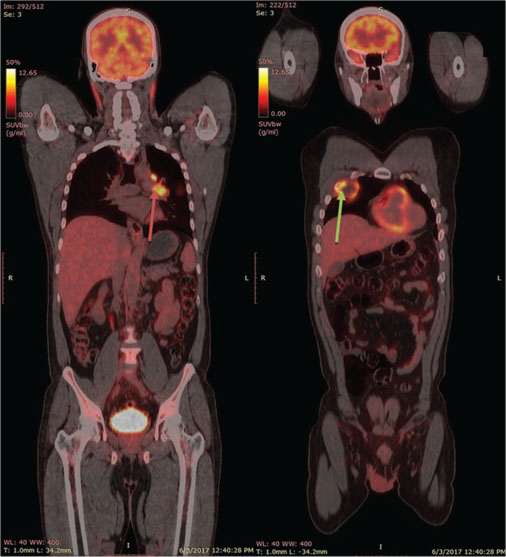

The HOP mass (8.3 cm × 6.2 cm × 6.2 cm) was more 68Ga-DOTA-NOC avid while the D1–D2 mass (2.4 cm × 2.9 cm) was more FDG avid [Figure 2].

| Figure. 2 Axial fluoro deoxycolic glucose positron-emission tomography and (1,4,7,10-tetraazacyclododecane-1,4,7,10-tetraacetic acid)-1-Nal3-octreotide positron-emission tomography image of the upper abdomen reveal large soft tissue intensely (1,4,7,10-tetraazacyclododecane-1,4,7,10-tetraacetic acid)-1-Nal3-octreotide avid and fluoro deoxycolic glucose positron-emission tomography nonavid mass in the head and uncinate process of pancreas (white arrows in image a, b, and c) and another polypoidal intraluminal fluoro deoxycolic glucose positron-emission tomography avid and (1,4,7,10-tetraazacyclododecane-1,4,7,10-tetraacetic acid)-1-Nal3-octreotide nonavid mass in D2 part of duodenum (dashed white arrows in image a, b, and c)